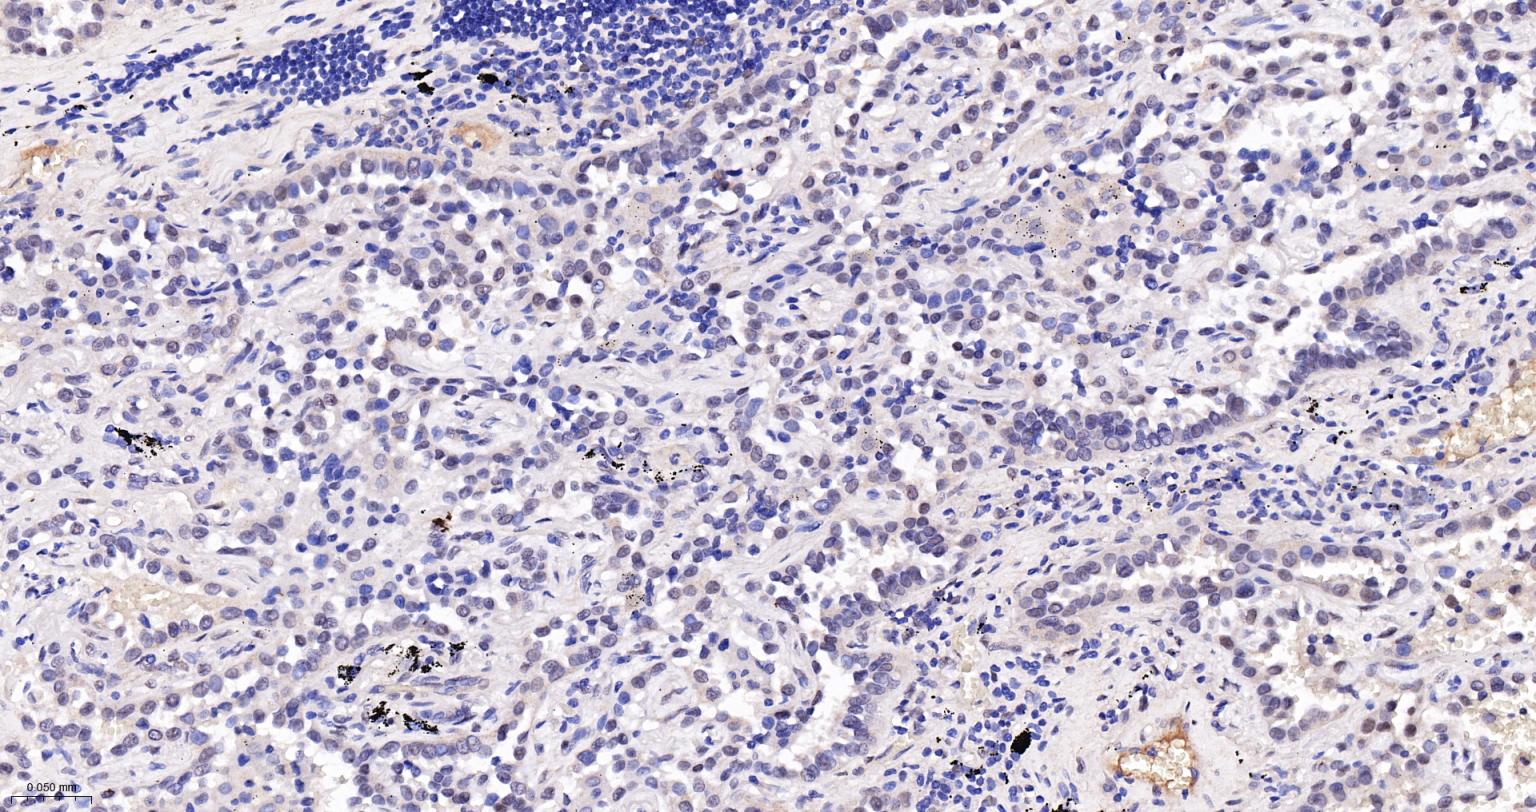

Paraformaldehyde-fixed, paraffin embedded Human Lung Cancer; Antigen retrieval by boiling in sodium citrate buffer (pH6.0) for 15 min; The section was incubated with TEAD1 Monoclonal Antibody, Unconjugated (bsm-63274R) at 1:200 overnight at 4°C, followed by conjugation to the bs-0295G-HRP and DAB (C-0010) staining.